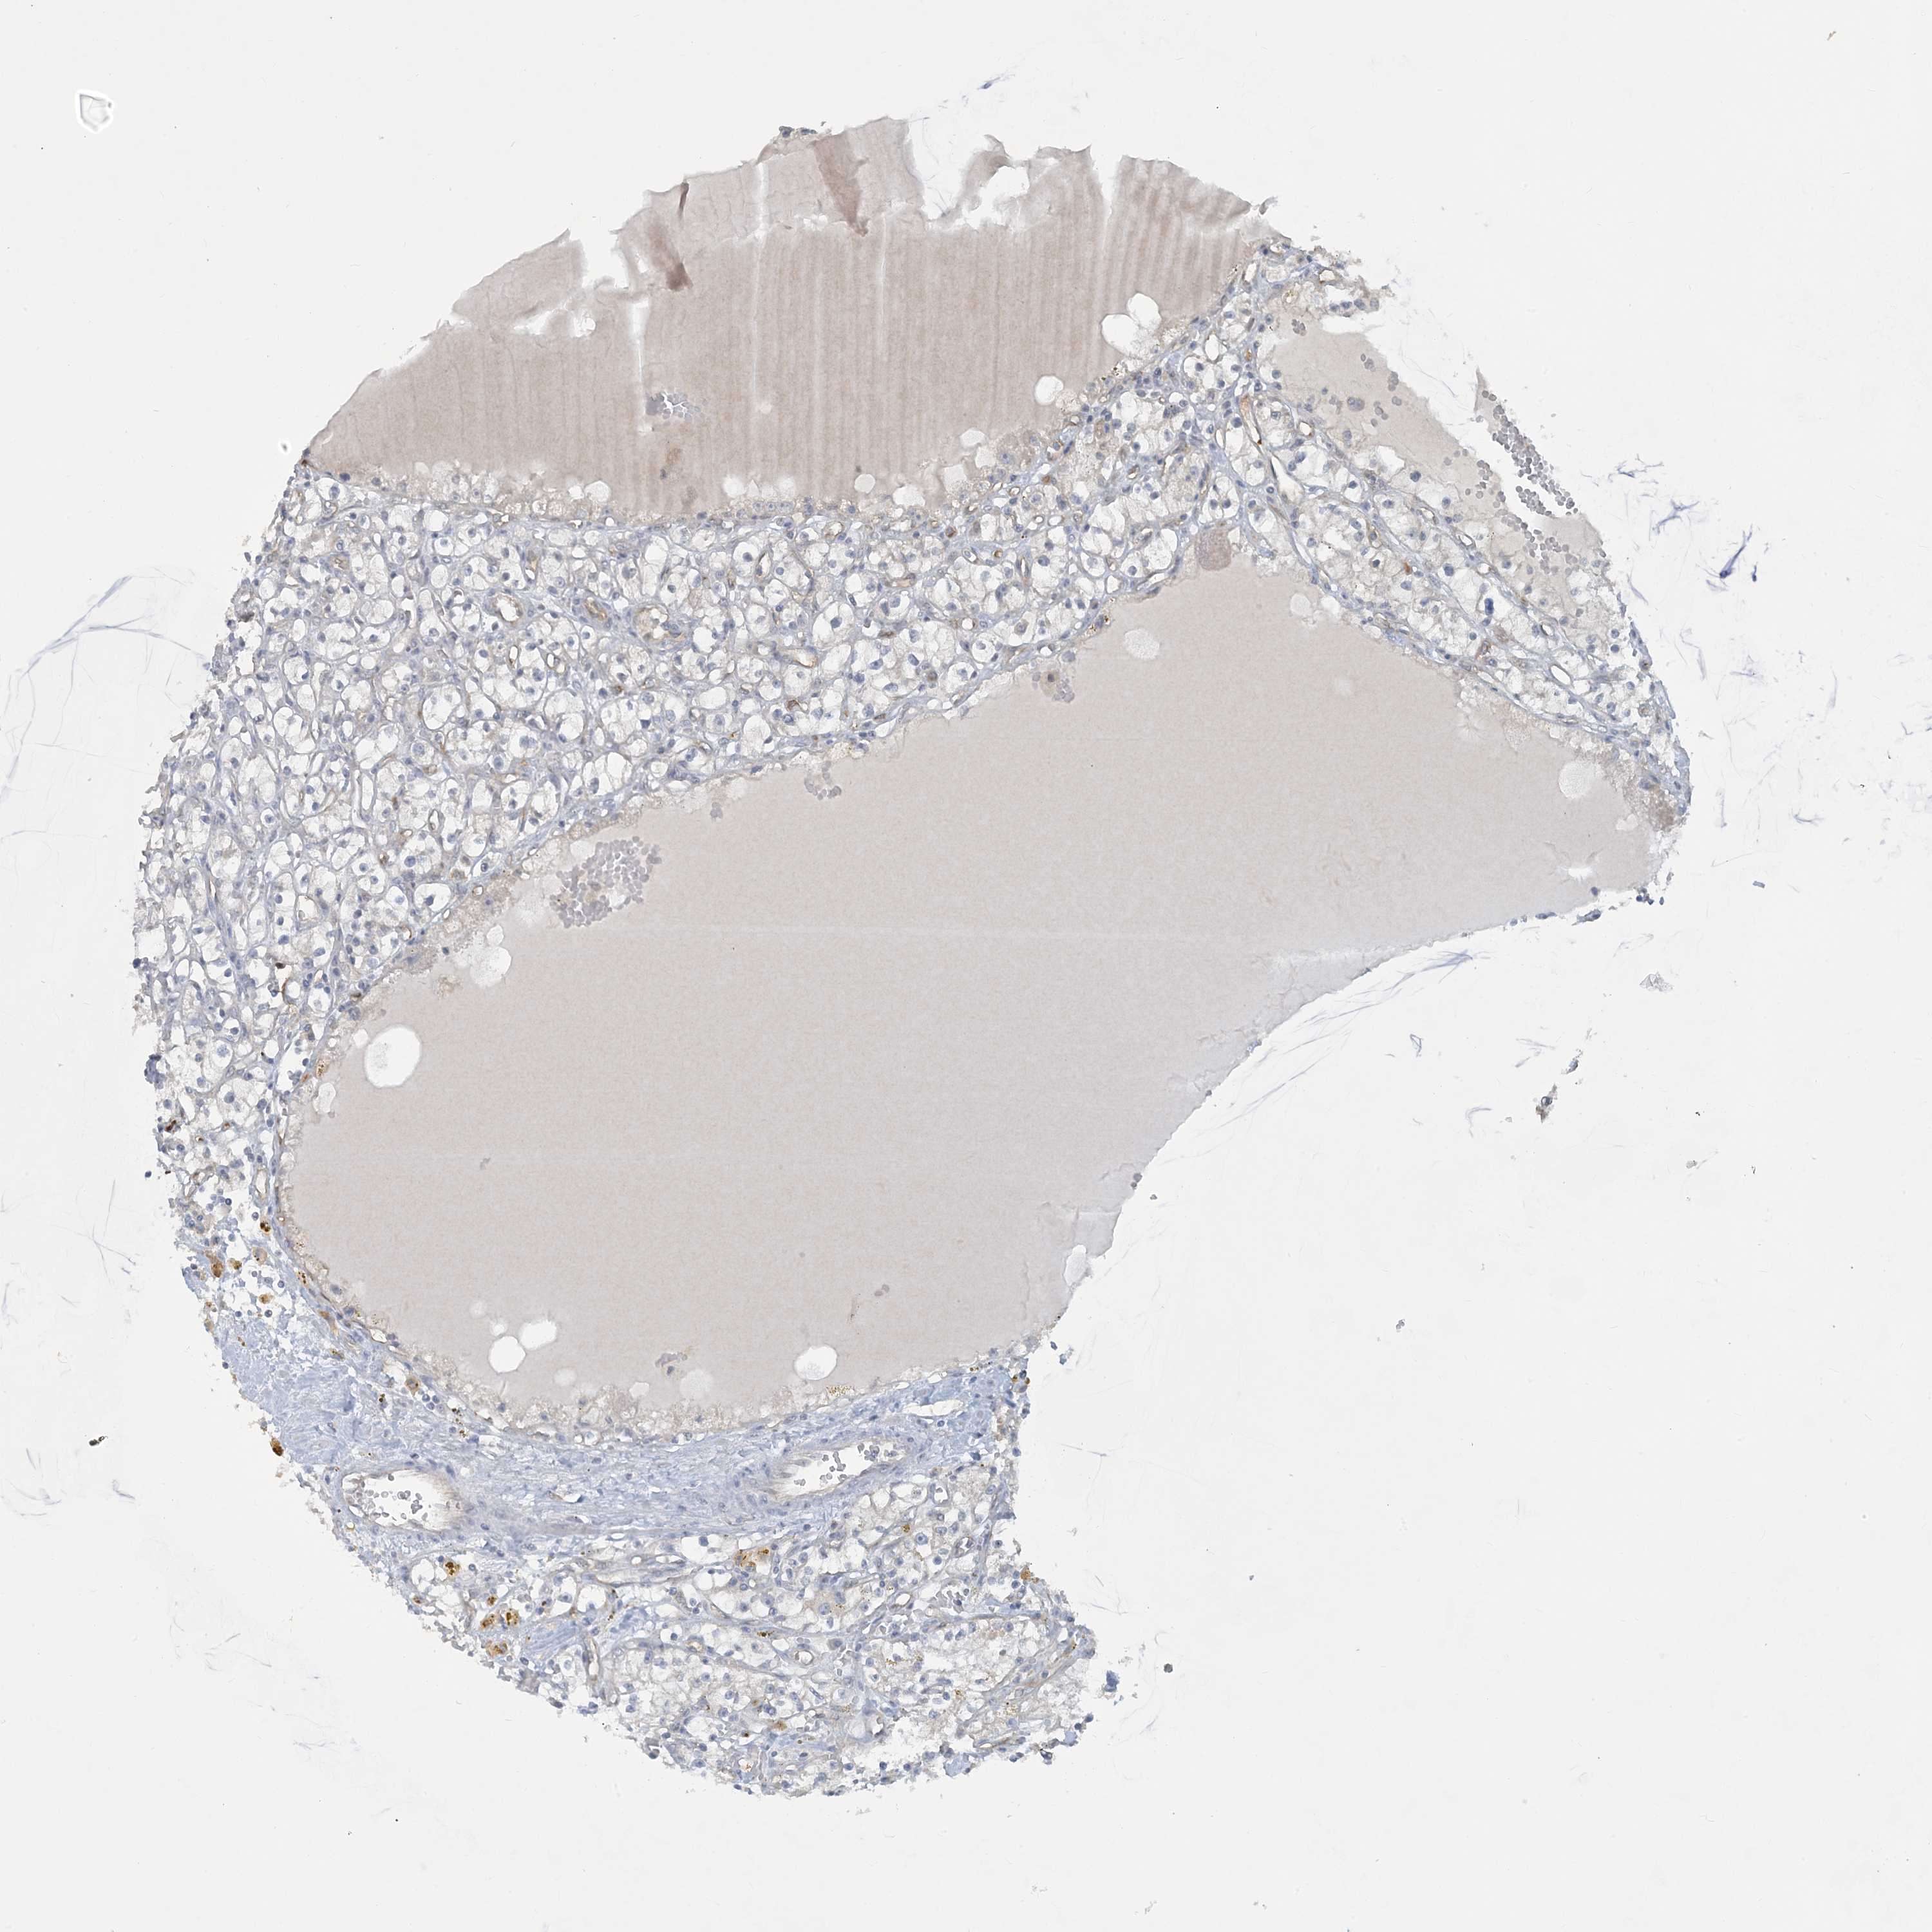

KIDNEY RENAL CLEAR CELL CARCINOMA (VALIDATION) - Interactive survival scatter ploti

The Survival Scatter plot shows the clinical status (i.e. dead or alive) for all individuals in the patient cohort, based on the same data that underlies the corresponding Kaplan-Meier plots. Patients that are alive at last time for follow-up are shown in blue and patients who have died during the study are shown in red.

The x-axis shows the expression levels (FPKM) of the investigated gene in the tumor tissue at the time of diagnosis. The y-axis shows the follow-up time after diagnosis (years). Both axes are complimented with kernel density curves demonstrating the data density over the axes. The top density plot shows the expression levels (FPKM) distribution among dead (red) and alive patients (blue). The right density plot shows the data density of the survived years of dead patients with high and low expression levels respectively, stratified using the cutoff indicated by the vertical dashed line through the Survival Scatter plot. This cutoff is automatically defined based on the FPKM cutoff that minimizes the p-score. The cutoff can be changed by dragging the vertical line or by entering a cutoff value in the square labeled "Current cut-off".

Under the Survival Scatter plot the p-score landscape (black curve; left axis) is shown together with dead median separation (red curve; right axis). Dead median separation is the difference in median mRNA expression between patients who have died with high and low expression, respectively. It is calculated as follows: median FPKM expression of dead patients with high expression - median FPKM expression of dead patients with low expression. This is intended to aid the user in visually exploring custom cutoffs and the associated p-scores and dead median separation.

Individual patient data is displayed and can be filtered by clicking on one or more of the category buttons on the top of the page. Categories describing expression level and patient information include: high, low, alive, dead, female, male and tumor stages. The scale of the x-axis can be toggled between linear and log-scale by clicking on the "x log" button. Mouse-over function shows TCGA ID, patient information and mRNA expression (FPKM) for each patient.

& Survival analysisi

Kaplan-Meier plots summarize results from analysis of correlation between mRNA expression level and patient survival. Patients were divided based on level of expression into one of the two groups "low" (under cut off) or "high" (over cut off). X-axis shows time for survival (years) and y-axis shows the probability of survival, where 1.0 corresponds to 100 percent.

CDS1 is validated prognostic, high expression is favorable in Kidney Renal Clear Cell Carcinoma (validation)

: 5.45

Average pTPM 10.1

Number of samples 100